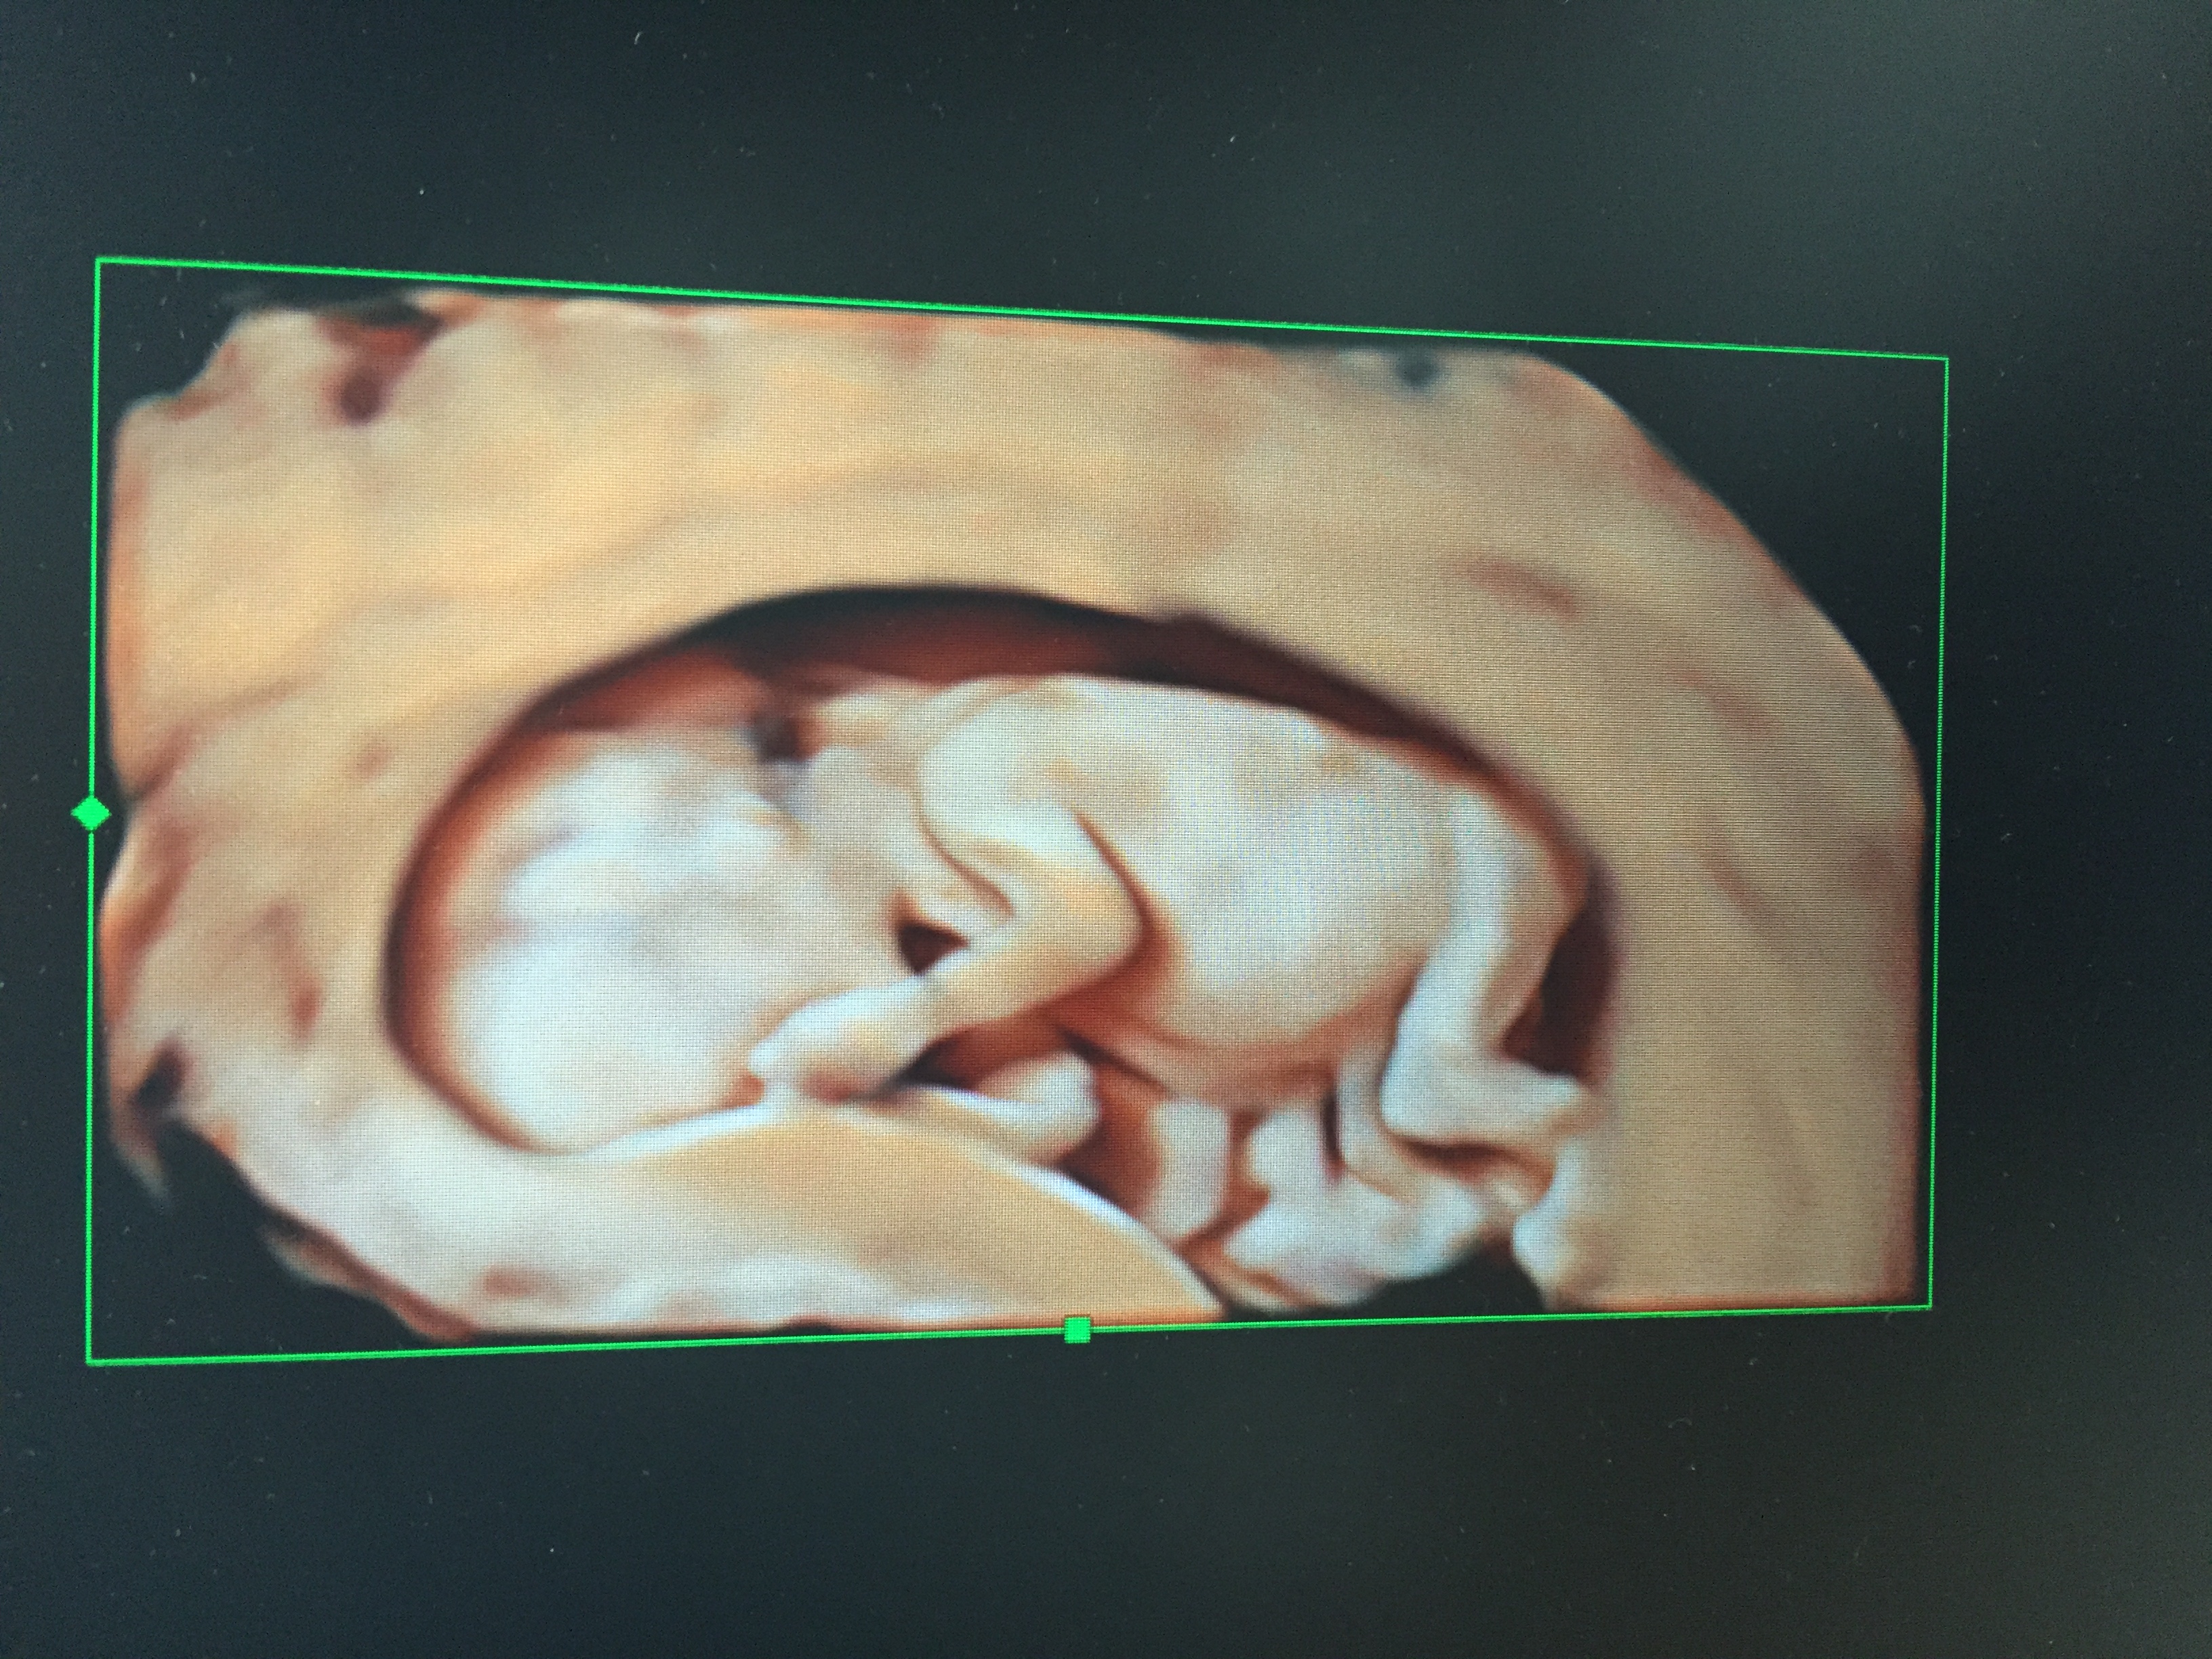

• Just had my NT scan today and she did a 3d one. Here's my little alien! 12 wks

BabyFruit Ticker BabyFetus Ticker